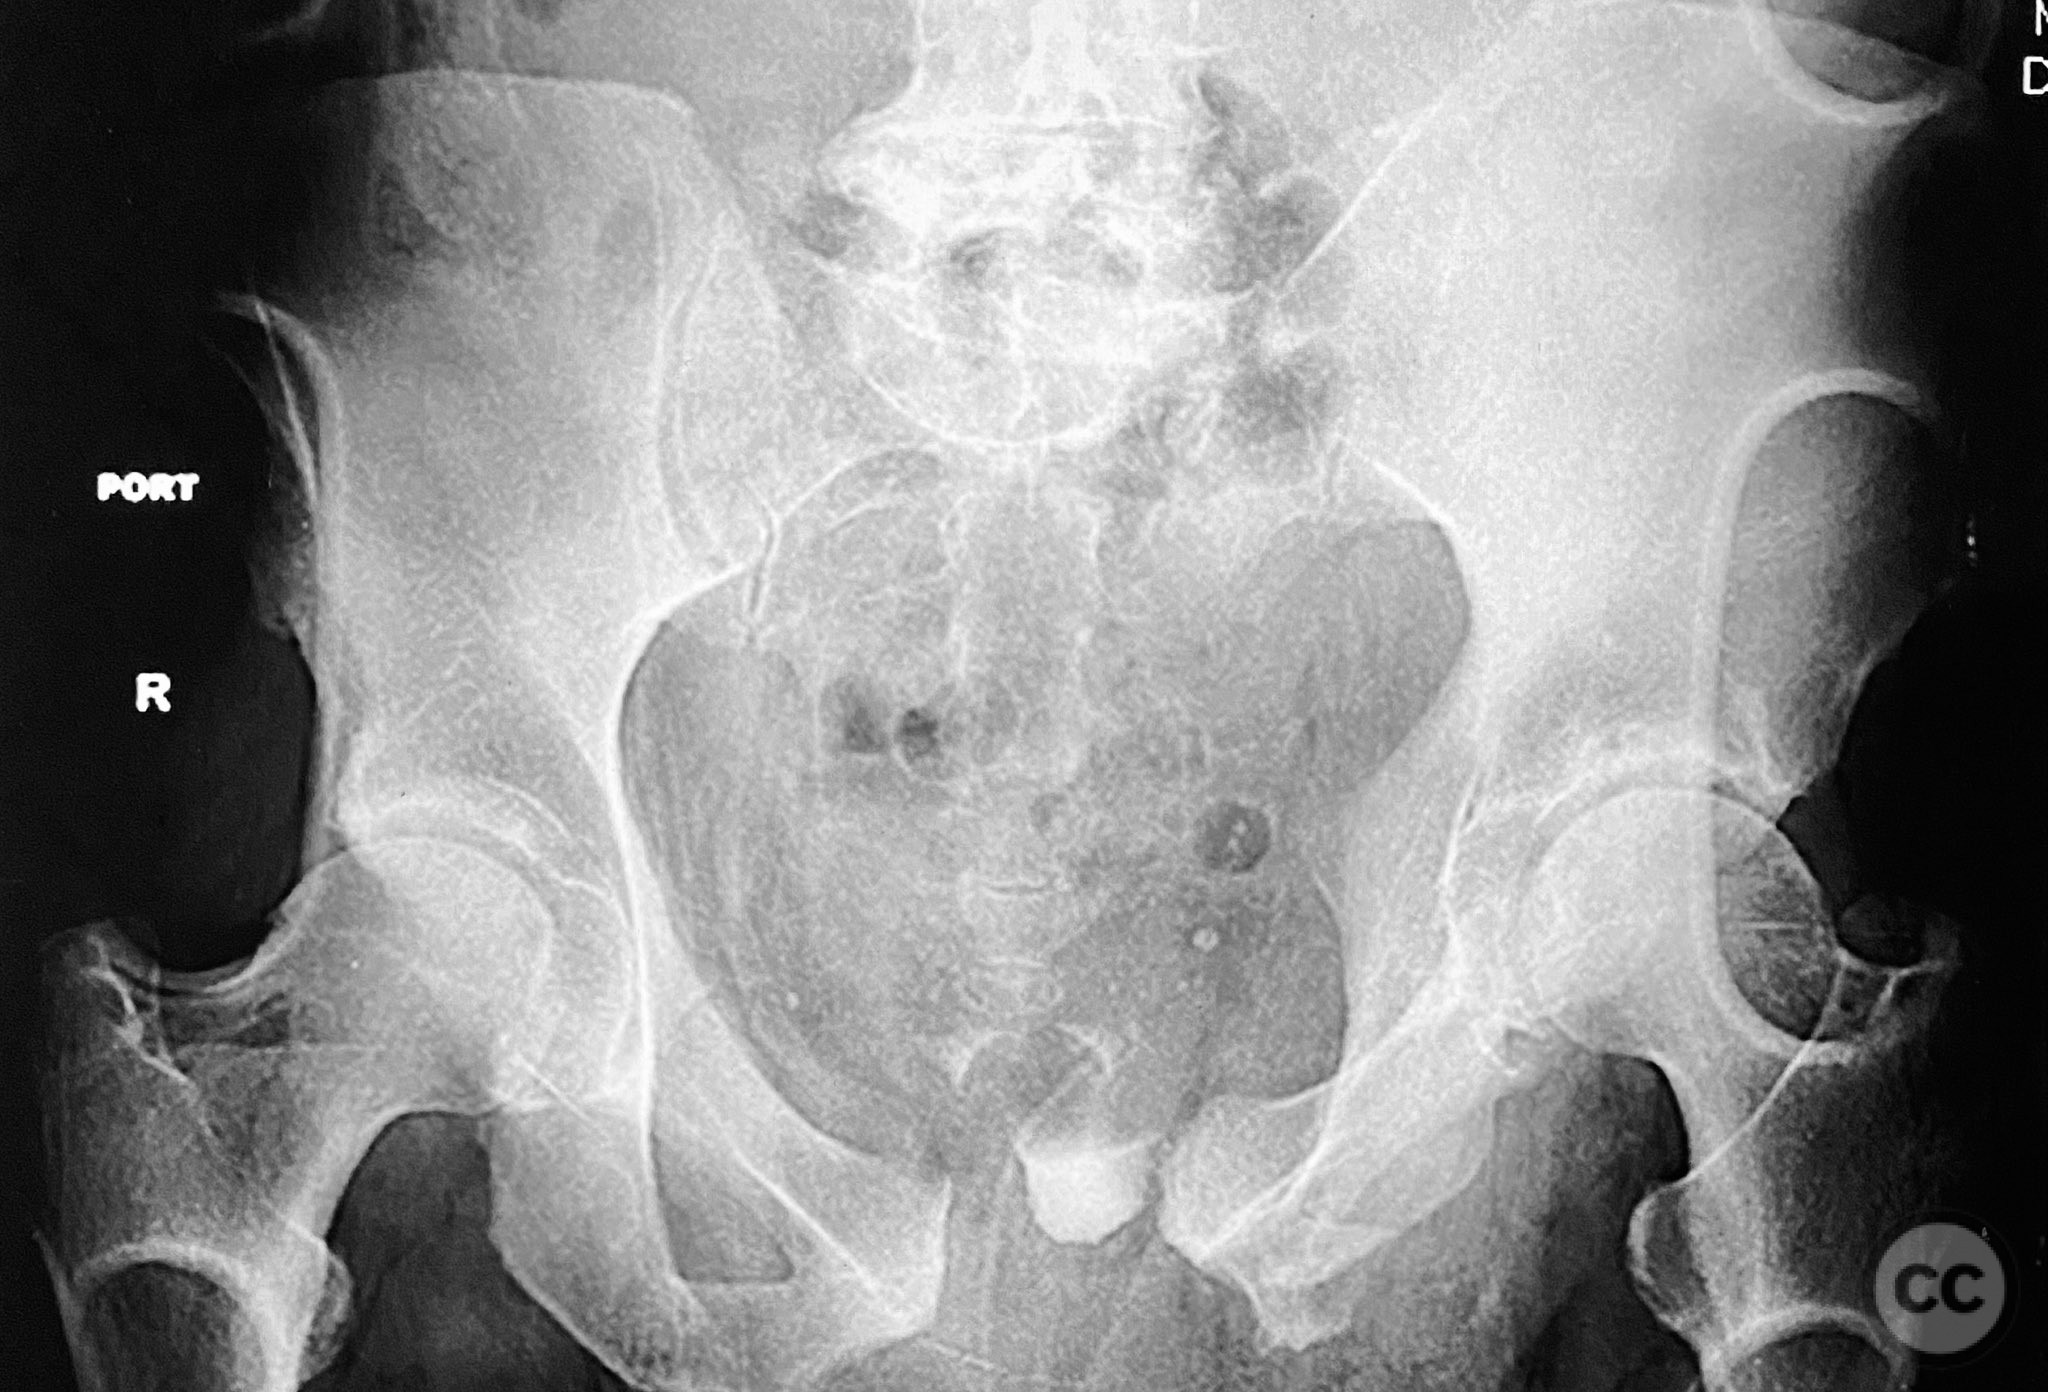

Clinical and radiological findings:  Middle-aged male with a high-energy pelvic ring injury, presenting with significant pain and mechanical instability. Initial radiographs demonstrated comminution and displacement of the posterior pelvic ring, including sacral fractures and disruption of the anterior ring at the pubic symphysis and rami. Application of a circumferential pelvic sheet provided partial reduction and improved comfort. No neurovascular deficits were noted. CT imaging confirmed a comminuted sacral fracture (AO/OTA 61-C1.3), with bilateral pubic rami fractures and symphyseal diastasis. The posterior elements demonstrated both vertical and rotational instability.

Planning remarks:  The preoperative plan involved staged management: initial prone positioning for open reduction and internal fixation (ORIF) of the sacrum, utilizing the dorsal cortical fracture edges for direct reduction and clamping, followed by percutaneous iliosacral screw fixation and a posterior transiliac screw. Definitive anterior ring stabilization was planned subsequently via open reduction and internal fixation of the symphysis and pubic rami through an anterior approach.